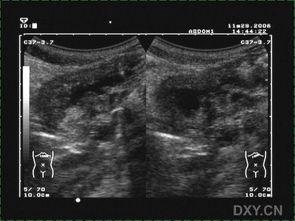

超声胃视频,顾名思义,就是利用超声波来观察胃部的一种检查方法。它的工作原理是这样的:医生会先让你喝下一杯含有微泡的液体,这些微泡会随着胃的蠕动而移动,从而产生回声。医生将超声探头放在你的腹部,通过调整探头与胃部的距离和角度,就可以清晰地观察到胃壁、胃腔、胃窦等部位的情况。

超声胃视频在临床上的应用非常广泛。它可以用于诊断胃炎、胃溃疡、胃息肉、胃癌等胃部疾病。此外,对于胃部手术后的患者,超声胃视频还可以用于观察胃部恢复情况。